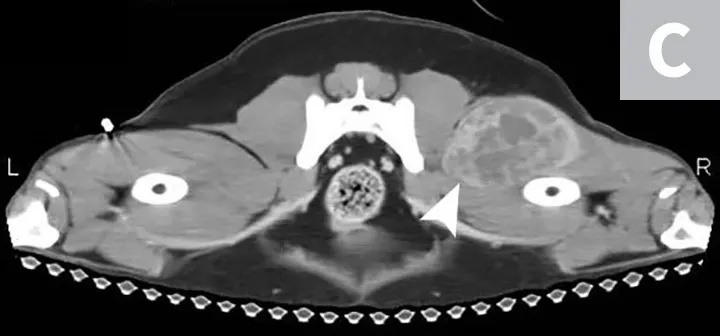

Definitive diagnosis of HSA requires microscopic identification of tumor cells through cytology or histopathology. Due to the poorly exfoliative nature of mesenchymal tumors coupled with the hemorrhagic nature of HSA, fine-needle aspiration cytology often produces samples of low cellularity with rare identification of malignant cells (Figure 4). Cytologic examination of hemorrhage effusions is not typically helpful or diagnostic for HSA because of the low numbers of neoplastic cells admixed with a large volume of blood. Biopsy is suggested for definitive diagnosis because benign lesions (ie, splenic hematoma) can have clinical presentations (ie, splenic mass with associated hemoabdomen) similar to malignant HSA. Excisional biopsy is preferred because it is diagnostic and therapeutic. All resected tissue samples should be evaluated for histologic features of malignancy and immunohistochemically stained for endothelial markers (eg, CD31).

FIGURE 4A

Cytology showing malignant mesenchymal cells with multiple criteria for cellular malignancy (eg, anisocytosis, anisokaryosis; A); histopathology of the splenic mass demonstrating malignant spindle cells forming haphazard and disorganized vascular channels (B) and strong positivity for the expression of CD31 (PECAM-1), which is represented by brown membranous staining of HSA cells and confirms that malignant cells are of endothelial origin (C). Images courtesy of Anne Barger, DVM, MS, DACVP, and Jonathan Samuelson, DVM, DACVP